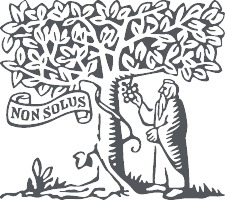

Además, podemos encontrar hipercaptaciones focales a diversos niveles, tanto óseas como extraóseas, que variarán en función de la patología concreta del paciente (figs. 1 y 2).

Fig. 1. Gammagrafía ósea con MDP-99mTc de cuerpo completo en paciente con enfermedad metabólica ósea. Se aprecian múltiples depósitos patológicos del trazador afectando fundamentalmente a parrillas costales y de forma muy importante sobre esternón. También se aprecian calcificaciones extraóseas.